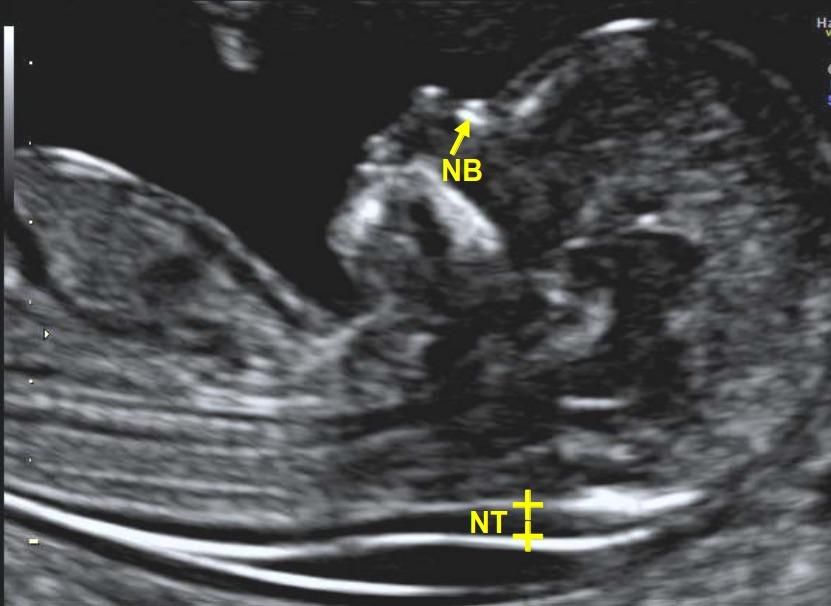

Nuchal translucency ultrasound is a screening test performed in the first trimester to measure fluid-filled space at the fetal neck. Increased thickness (>3.5 mm at 11–14 weeks) is associated with chromosomal abnormalities such as trisomy 21, 18, and 13, as well as structural defects like congenital heart disease. Normal nuchal translucency is <3.5 mm. This non-invasive test, when combined with maternal serum markers, improves early detection of fetal anomalies.

Rationale for correct answers

2. Nuchal translucency ultrasound specifically measures the subcutaneous fluid accumulation at the back of the fetal neck between 11–14 weeks gestation. Increased measurements are linked to chromosomal and structural abnormalities.

- Nuchal translucency ultrasound measures fluid at the fetal neck.

- Increased thickness (>3.5 mm) indicates higher risk of chromosomal and structural defects.